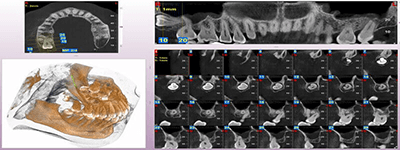

We practice the ALARA principle; (As low as Reasonably Achievable) all scans are restricted to the “Field of View” of your dentist’s prescription. It is taken using (1) pulsed x-ray exposure protocols, (2) real-time-automatic exposure control of the x-ray dose based on the patient’s actual bone density & (3) high resolution digital x-ray image sensors. These factors lead to a significant reduction in x-ray exposure equivalent to only 10% of the x-ray dose of a medical CT-Scan.

The aforementioned technology is inherent in the “myRay X9 CBCT Scan” that we use. myRay X9 is an Italian-made Oral Maxillofacial CT-Scan, certified compliant by European, Japan, USA and other international authorities in radiation safety.

Proactive Dental Management thru our 3D Imaging Manipulation Software

With Oral Maxillofacial CT Scans, your dentist enhances his ability to proactively manage your health concern thru accurate diagnosis & better treatment planning. Moreover, the patient benefits from a painless,low radiation dose CT Scan procedure.